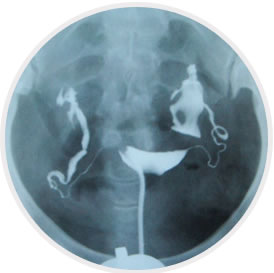

输卵管造影